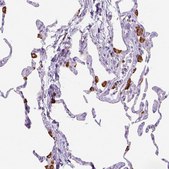

Anti-CD68 antibody produced in rabbit

immunohistochemistry: 1:2500-1:5000

- IHC tissue array of 44 normal human tissues and 20 of the most common cancer type tissues.